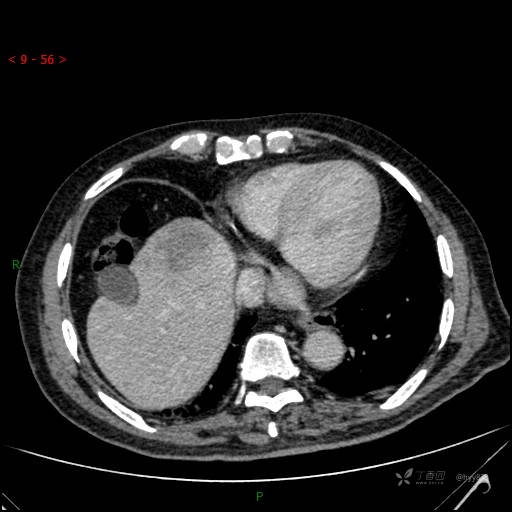

肝脏CT平扫

img